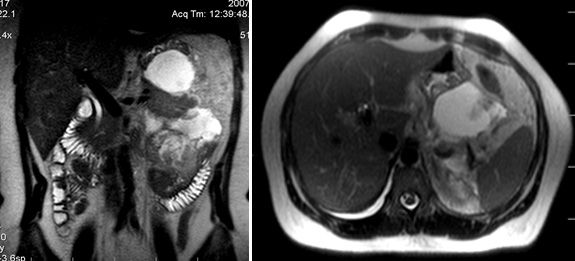

- МРТ поджелудочной железы и окружающих тканей позволяет оценить распространенность опухолевого процесса.